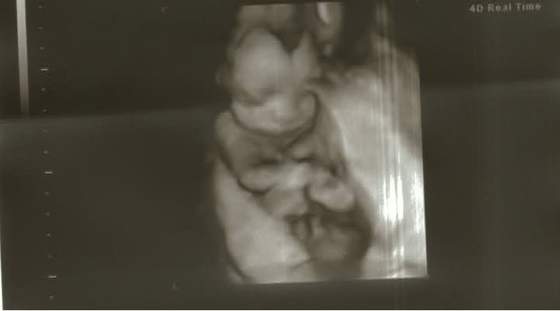

Chciał mi zrobić ładne zdjęcie buźki, ale wtulał się w łożysko i nic nie pomogły stukania i mówienie do monitora mojego lekarza